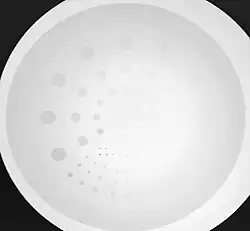

The maximum spatial resolution of an imaging system can be readily obtained by imaging a resolution test object - an example of which is shown in Figure 6.5, panel (a). The test object consists of narrow parallel slits in a lead sheet at spacings which decrease to beyond the maximum resolution of the image receptor. The minimum spacing resolved in images is called the Limiting Spatial Resolution and can be determined to be about 3.5 line pairs/mm from the figure.

- Contrast-detail evaluation combines physical indices of image quality with observer detection ability. Contrast-detail phantoms contain test objects of different sizes and subject contrast mounted on a plastic plate that is radiographed under specific exposure conditions - see Figure 6.20. Contrast-detail plots are derived on the basis of the borderline visibility of test objects in the image. A disadvantage of this approach however is the introduction of bias as a result of the observer's prior knowledge of the size, shape and location of the low-contrast objects. The link between this type of evaluation and clinical imaging performance is therefore difficult to establish.